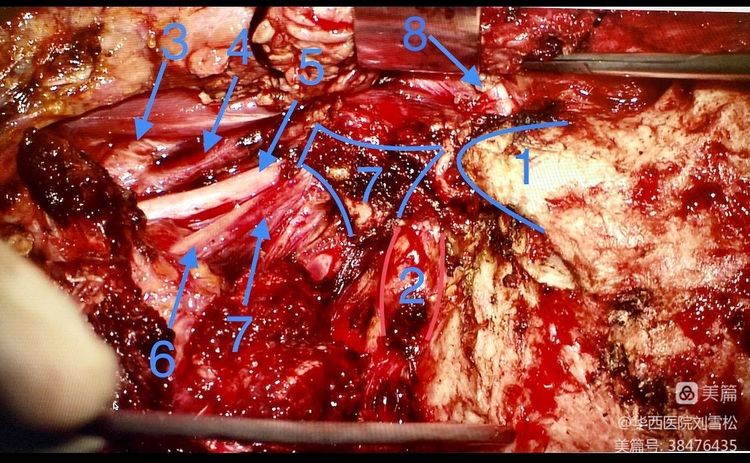

蓝色箭头指出C-1横突阻挡位于其前方的部分瘤体

图中:1、乳突尖 2、椎动脉 3、颈内动脉 4、颈外动脉 5、迷走神经 6、副神经 7、颈内静脉 8、面神经 9、C-1横突

头外侧直肌附着于C-1横突前方和颈静脉突的位置,磨除C-1横突,乳突尖,并将头外侧直肌向下游离后即可暴露颈静脉突,将其磨开就能暴露颈静脉孔向颈部走行的肿瘤操作最狭窄区域。

暴露面神经垂直段后可见肿瘤紧贴面神经并将其向后推挤,术中打开茎乳孔并做垂直段前移位

前移面神经后,磨除颈静脉突暴露肿瘤全程

延肿瘤边界整块分离切除肿瘤,在颈静脉孔内有多个出血的静脉孔道用明胶填塞止血。全切肿瘤后暴露完整瘤腔。